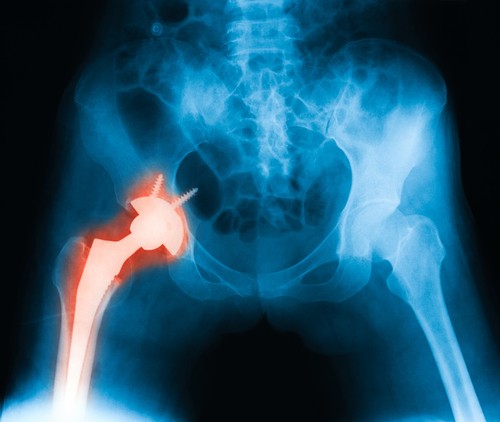

Titán csontpótlásokat fejlesztenek, amik teljesen összépülnek a csonttal - az ábrán a hagyományos, csavaros módszer látszik.

A professzor kiemelte: cél, hogy olyan implantátumokat tudjunk készíteni, amelyeket nem csavarok és egyéb műszaki megoldások tartanak, hanem összeépülnek a csonttal.